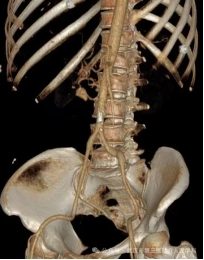

紧急的增强CT检查结果,证实了我们的最坏猜想:肠系膜上动脉的一个分支上,有一个动脉瘤破裂了! 血液正从破口不断涌入腹腔。

精准导航:在DSA透视的引导下,我们像“巡航导弹”一样,将一根细长而柔软的导管,从股动脉一路精准地“行驶”到肠系膜上动脉,最终抵达破裂的动脉瘤分支。

封堵“决堤口”:通过导管,我们向破裂的动脉瘤及其两端释放了数枚微小的 “弹簧圈” 。这些弹簧圈会迅速在破口处盘绕成团,形成一个致密的“塞子”,瞬间堵死破口,让血液无法再流出。

手术成功了! 屏幕上显示,破裂的血管不再造影剂外溢。这意味着,“决堤口”被成功封堵。整个过程,患者体表只有一个针眼大小的伤口。术后,王先生的血压很快稳定下来,脱离了生命危险。